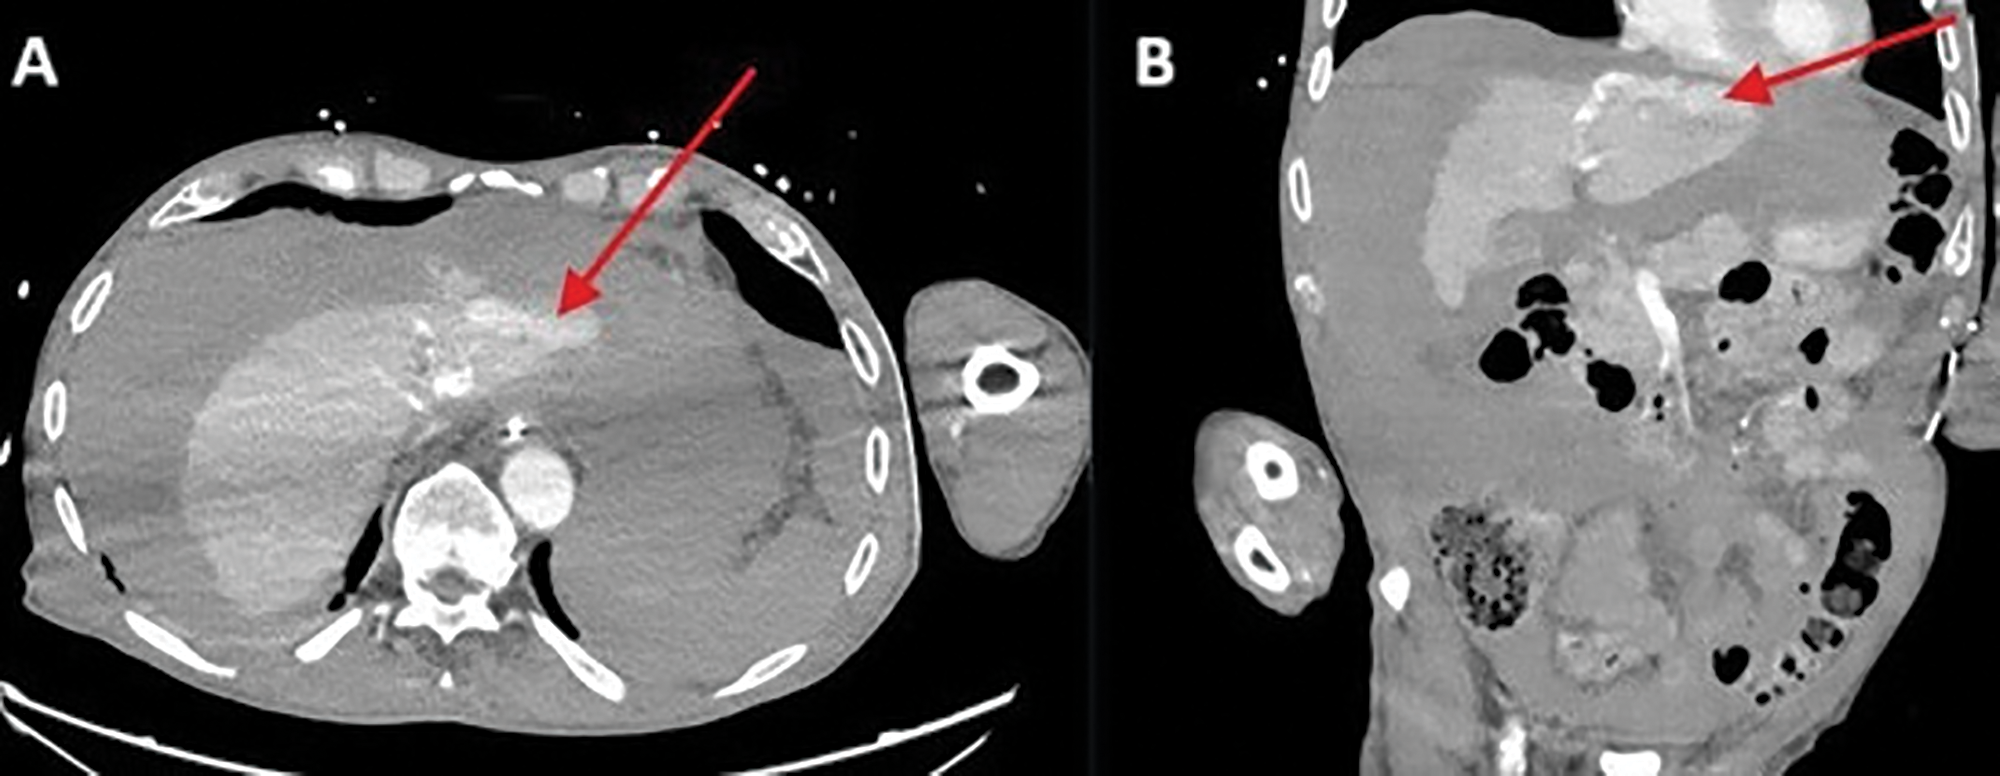

Figure 1

Active venous contrast extravasation against the left hepatic lobe.